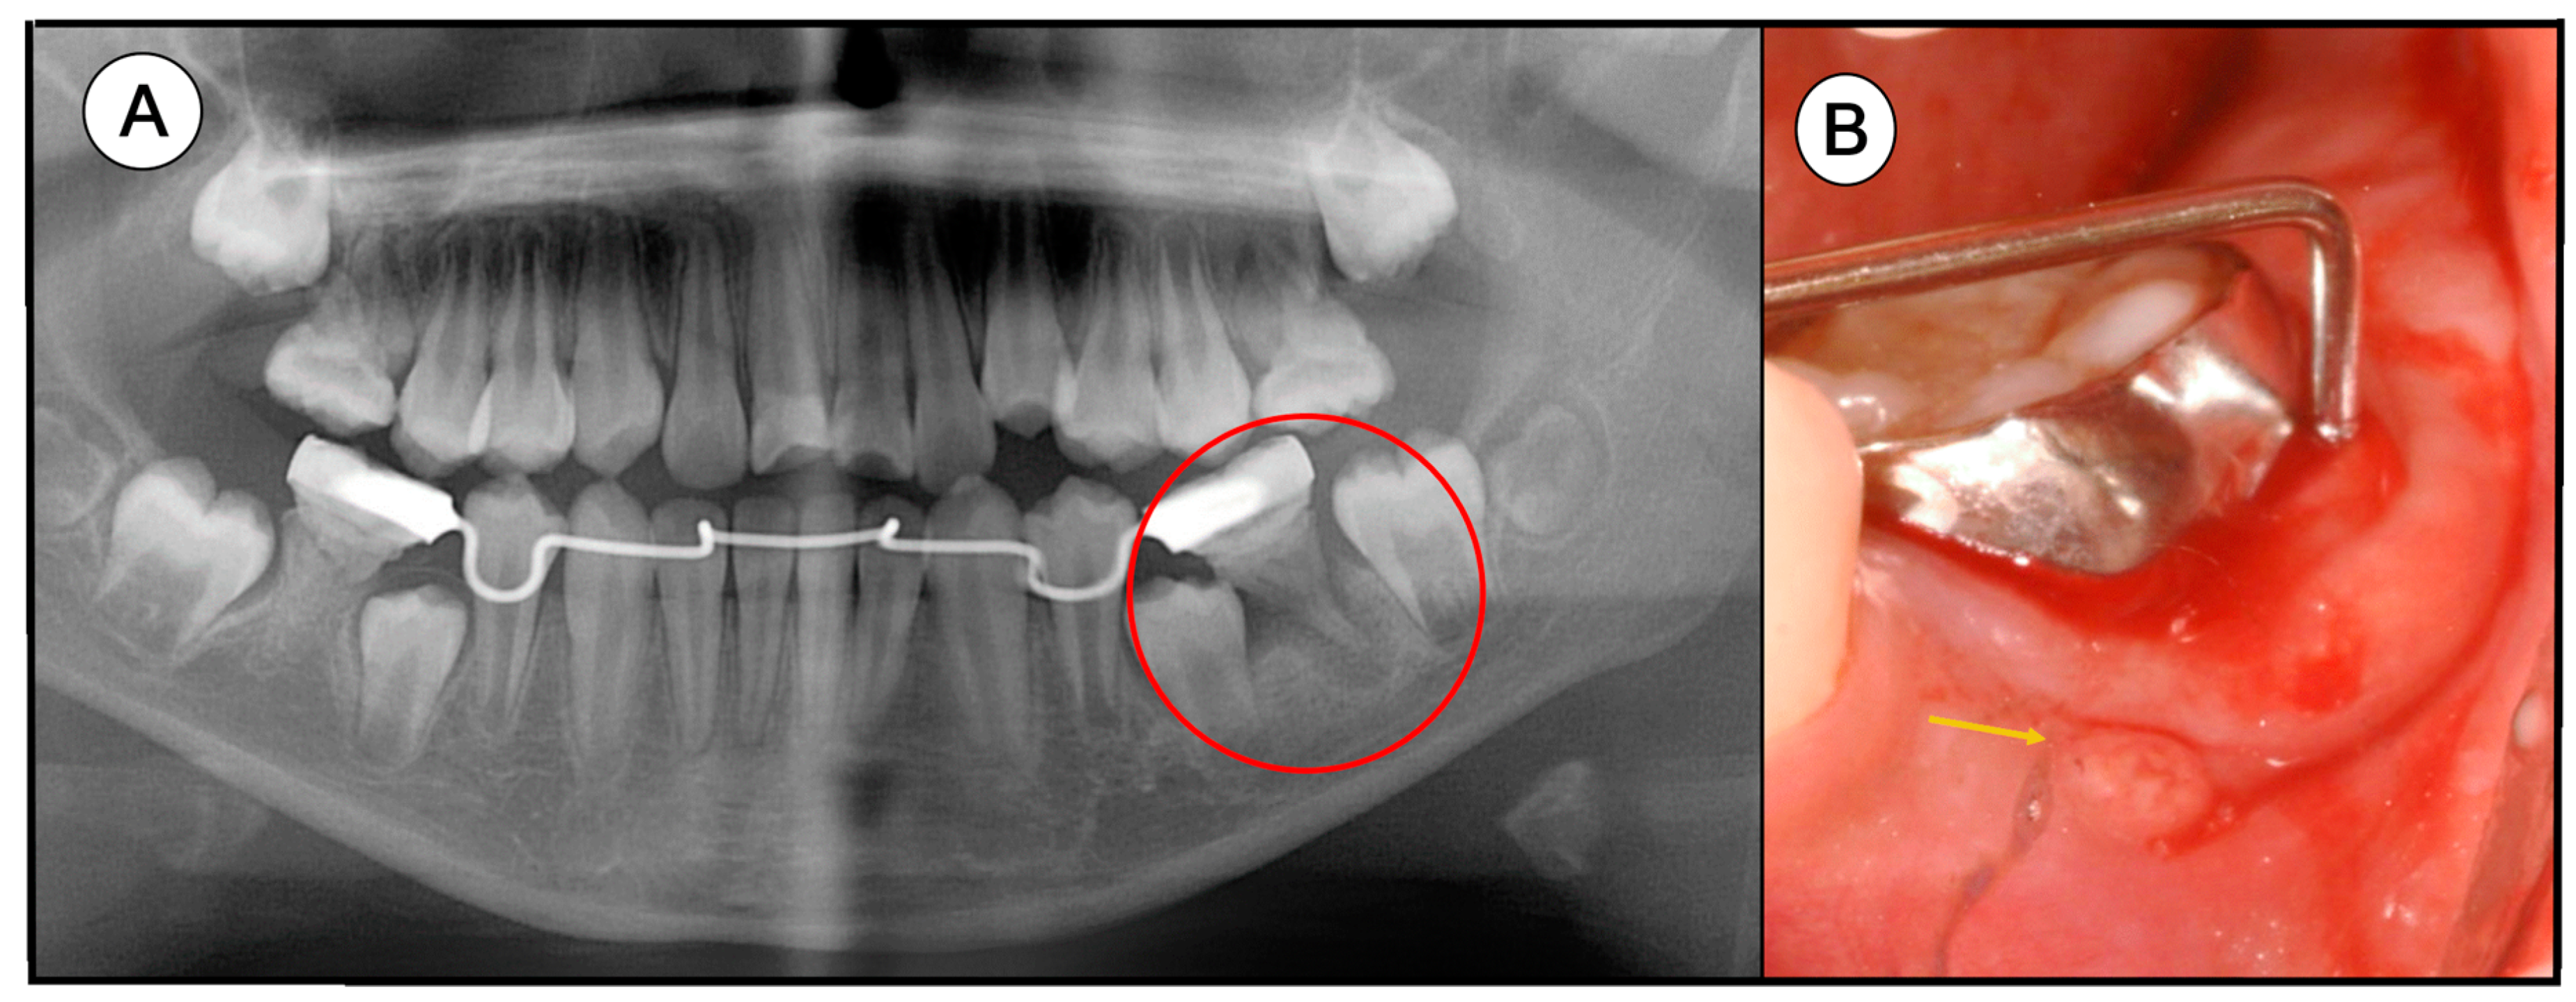

When the patient was 10, severe dentoalveolar infection and fistula occurred on the mandibular left first molar (Figure 2). Orthodontic analysis was conducted for treatment planning. She already had a space discrepancy and we decided to extract all permanent first molars affected by MIM and perform orthodontic treatment after the eruption of the secondary molars. Thereafter, the four MIM first molars were extracted sequentially and they showed twisted roots with granulation tissue (Figure 3). The crown and root of the maxillary left molar and mandibular right molar were fractured during the extraction. One year later, the second molars erupted and were relatively well-aligned.

Figure 2. Clinical photos. (A) Two years later, a severe dentoalveolar abscess was observed on the mandibular left first molar. (B) The full depth of the distobuccal region was probed and a fistula was seen (yellow arrow).